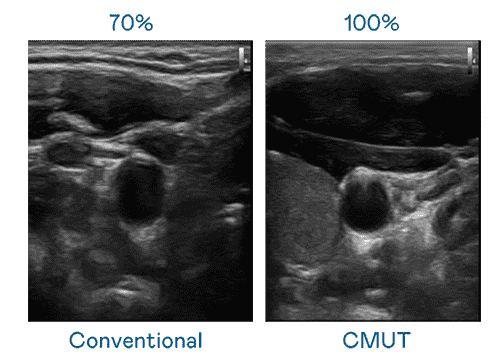

CMUT 技术是一种用电容式微机电元件来产生超音波讯号的技术。。。与传统 PZT 压电式技术相比,,,CMUT 频宽增加 30%,,,更宽频的超音波讯号让影像解析度大幅提升,,,,是实现高影像品质医疗超音波扫描、、促进精准医疗发展的关键技术。。。。

大频宽带来超清晰影像

超音波影像的解析度高低,,,首先取决于探头能发出的讯号频宽。。。菠菜论坛 CMUT 可提供高清晰的超音波讯号,,,,提供高频宽、、、高灵敏度、、、影像纹理细节更高的超音波影像,,,,协助医护人员缩短影像判读时间及利用精准的医疗影像进行诊断。。